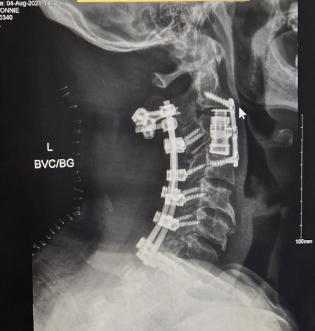

On 20 July 2025, while riding familiar jumps at Palm Bay’s Grapefruit Trails with fellow Brevard Mountain Bike Association (BMBA) members, Donnie crashed and severely broke his neck at the base of his skull, the C2 vertebrae...known as the "hangman's break." Helicopter medics flew him to the hospital’s trauma bay where surgeons spent 12 hours placing rods, screws and plates to fuse his vertebrae C2-C7 together and placed a stent in a 90 % blocked artery...the other one couldn't be repaired and was blocked off for now; additional major surgical repairs await once he’s stronger. Think about no ability to look up or down or to turn your head in either direction...you'll get a small glimpse of what Donnie's experiencing now.